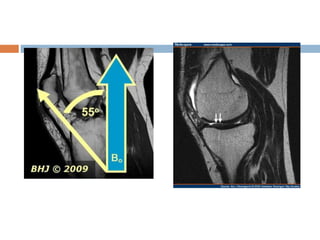

Magic angle artifact

 Seen most frequently in tendons and ligaments that

are oriented at a 55 degree to main magnetic field.

 Normally dipolar interaction between water

molecules in ligaments are strong.

 Which implies that T2 relaxation is very fast leading

to signal loss.

 Dipolar interaction go to zero.

 Solution

 Lengthen TE

 Use T1 weighted sequences since T1 relaxation is

unaffected by this.

• 29.

Magic angle artifact Seen most frequently in tendons and ligaments that are oriented at a 55 degree to main magnetic field.  Normally dipolar interaction between water molecules in ligaments are strong.  Which implies that T2 relaxation is very fast leading to signal loss.  Dipolar interaction go to zero.  Solution  Lengthen TE  Use T1 weighted sequences since T1 relaxation is unaffected by this.